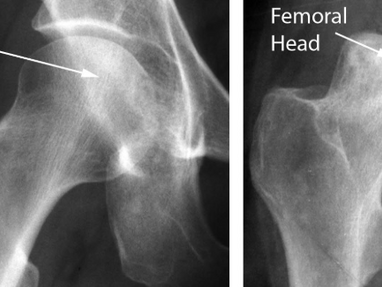

Osteonecrosis is a serious condition that affects the bones, leading to their gradual death due to insufficient blood supply. This can...